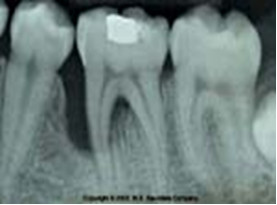

Dla jakiego rozpoznania periodontologicznego jest charakterystyczny przedstawiony obraz radiologiczny?